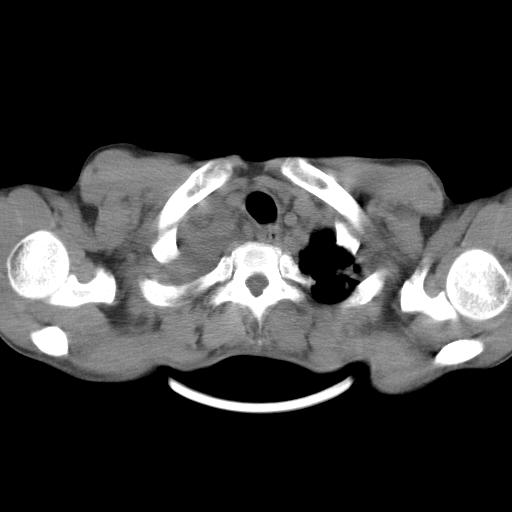

男性,44岁,结核病史多年。现胸闷气短,咳嗽,偶咳血。

双肺多发结节影最分空洞形成考虑占位不除外结核

1、右侧大量胸腔积液伴右肺压缩性膨胀不全,建议抽液治疗后复查 2、两肺继发性tb伴空洞形成。

1)两肺继发性肺结核伴空洞形成,左肺多发性结核球。2)右侧大量胸腔积液伴右肺部分膨胀不全。3)纵隔淋巴结肿大。

1,双肺多发结节 并空洞影改变, 左侧胸腔积液并部分包裹, 结合原病史首先考虑结核. 但也不除外其它.

2,左侧有一根肋骨陈旧性骨折? 建议追查 .

吉大一院胸水抽检结果:结核性胸水